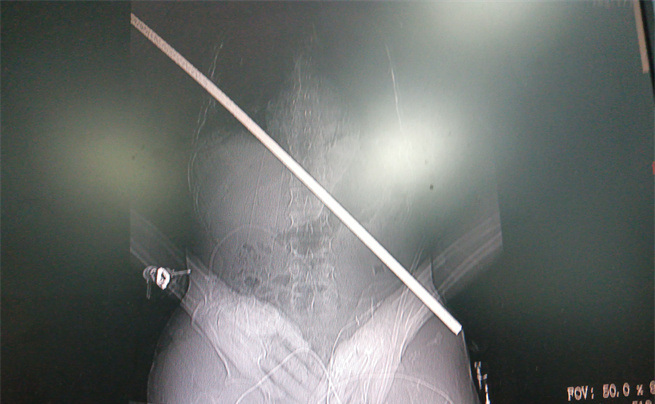

男子身上取出的鋼筋

“趕快救人!”工友們立即跑下來,檢查他的情況,只見鋼筋從右胸貫進(jìn)身體,末端到達(dá)左下腹,把皮膚頂起,只差一點(diǎn)就完全穿透身體了。大家從未見過如此慘烈的受傷情景,在安撫龍成的同時(shí),迅速撥打急救電話。

影像圖。大坪醫(yī)院供圖

術(shù)中,打開胸腔和腹腔,發(fā)現(xiàn)傷者右肺臟已被鋼筋穿透,鋼筋緊貼脊柱,隔肌、橫結(jié)腸及小腸系膜等被貫通,幸運(yùn)地是鋼筋避開了心臟,從下腔靜脈后方、腹主動(dòng)脈前方穿過。術(shù)中還由消化內(nèi)科文良志副教授行胃鏡檢查排除了食管損傷。放射影像科曹瑞、王承諾技師利用先進(jìn)的移動(dòng)CT在手術(shù)室行頭顱CT檢查進(jìn)一步排除了嚴(yán)重的顱腦損傷。

由沈岳教授親自緩慢拔出體內(nèi)長(zhǎng)達(dá)67厘米的鋼筋。隨后,各組專家各司其職,輪番上陣,為其修補(bǔ)好肺臟、隔肌、腸系膜等破損處。讓大家揪心的是,術(shù)中,病人曾雙側(cè)瞳孔變大,生命體征一度危急,經(jīng)醫(yī)生努力又將病人從鬼門關(guān)拉了回來。